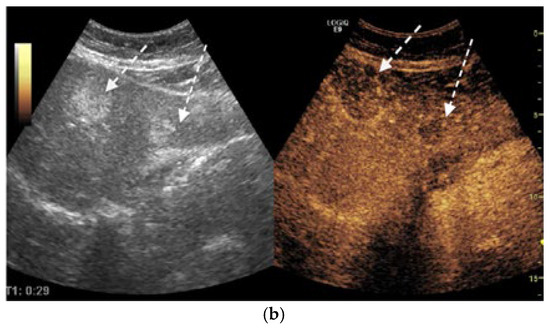

Synchronous Pulmonary and Cecal High-Grade Neuroendocrine Carcinomas Presenting as Hepatic Metastases: A Diagnostic Challenges and Literature Review

Background and Clinical Significance: Neuroendocrine neoplasms (NENs) are a group of malignancies that may remain clinically silent for many years. The presence of hepatic metastases can be the first clue leading to diagnosis. Case Presentation: We report the case of a 67-year-old man [...] Read more.

Background and Clinical Significance: Neuroendocrine neoplasms (NENs) are a group of malignancies that may remain clinically silent for many years. The presence of hepatic metastases can be the first clue leading to diagnosis. Case Presentation: We report the case of a 67-year-old man with intermittent tiredness and suspicious hepatic nodules detected on routine abdominal ultrasound. Contrast-enhanced ultrasonography showed arterial hyperenhancement with early washout, suggestive of metastases. Synchronous high-grade neuroendocrine carcinomas (NECs) of the lung and cecum were identified. Although the liver lesions were initially presumed to arise from the cecal tumor, liver biopsy immunohistochemistry was TTF-1 positive/CDX2 negative, whereas the cecal lesion was TTF-1 negative/CDX2 positive. This mutually exclusive immunophenotype confirmed two separate primary carcinomas. Given the high-grade histology, the patient received platinum-based chemotherapy and achieved a partial response. Conclusions: This case illustrates the diagnostic complexity of synchronous lesions and highlights the “mirage of the first lesion” phenomenon, in which the initially detected tumor may not represent the true primary site. A comprehensive, multidisciplinary strategy is crucial for establishing the correct diagnosis and guiding optimal management. Full article

(This article belongs to the Special Issue Diagnosis and Management of Neuroendocrine Tumors)